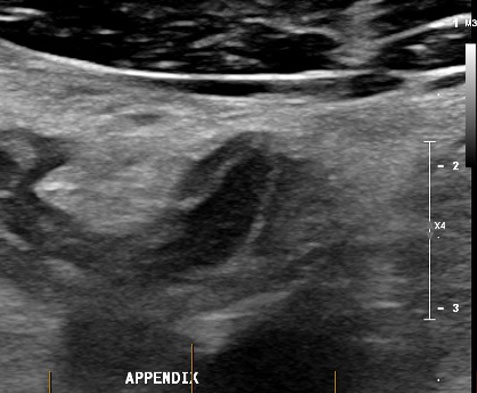

An 89-year-old man was admitted to the Department of Urology for testicular swelling and tenderness for five months with associated comorbidities of urolithiasis, atrial fibrillation in oral anticoagulant therapy, pleuritis, and hypertension. His testicular tumor markers [alpha-fetoprotein (AFP), beta-human chorionic gonadotropin (β-hCG), and lactate dehydrogenase (LDH)] were normal. A physical examination revealed a right testicular mass with normal skin and left testicle without abnormalities. Scrotal ultrasound (Figure 1) showed the presence of a large (4.16 × 2.26 cm) tumor with circular dichroism (CD) signal occupying the whole right testicle with heterogeneous echogenicity and smaller anechoic cystic components with minimal presence of normal testicular tissue. The left testicle was normal. A total-body computed tomography (CT) scan was performed and showed no signs of metastatic disease or lymphadenopathy. On suspicion of testicular cancer a right-sided radical orchiectomy was performed. Surgery was uncomplicated and he was discharged the day after the surgery. The patient had a close 12 month follow-up without need of any therapy and was in good condition 22 months after surgery.

Figure 1: Ultrasonic appearance of a right-sided tumor with far heterogeneously echogenic and cystic areas.